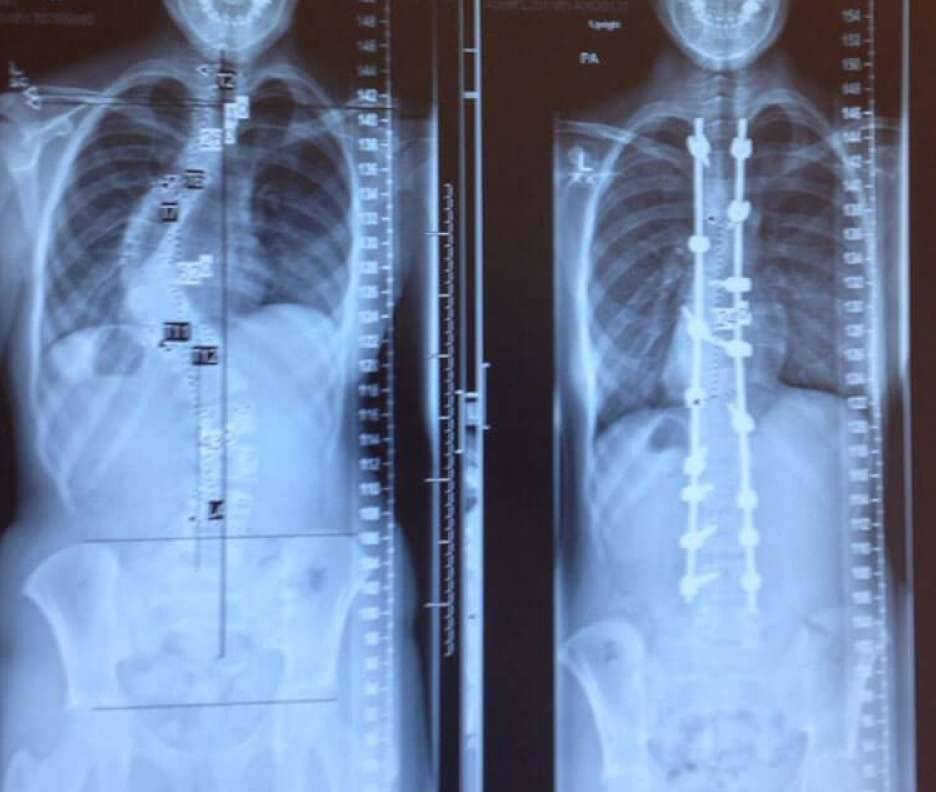

▼4. 脊椎侧弯症患者在治疗前后的X光图。